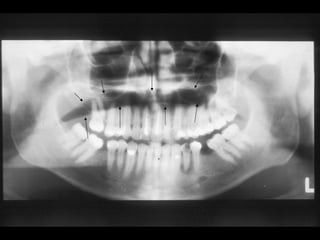

Lỗi khi chụp

Bóng của áo chì

Bóng của cột sống, thường do

bệnh nhân không đứng thẳng lưng